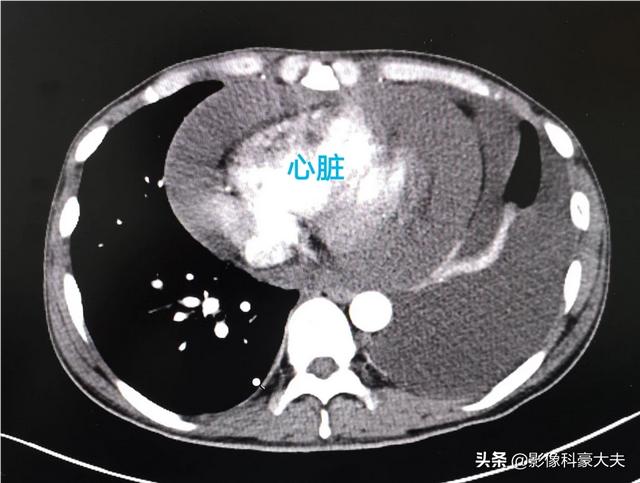

但这次CT显示癌细胞已经全面扩散。发生了胸腔积液、心包积液、骨转移、肝转移。状态已经很差了……

所以肺癌的早期筛查很重要。早期可以治愈!筛查首选胸部螺旋CT。可以及时发现有风险的肺结节。